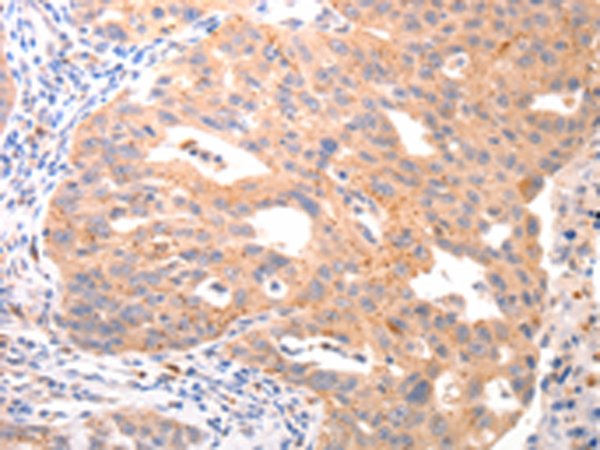

分类: 科研抗体货号: P10736别名: MCP-4, NCC1, CKb10, NCC-1, SCYL1, SCYA13应用: IHC反应种属: Human